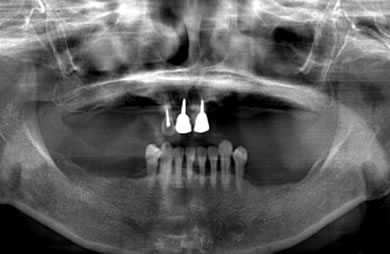

骨再生スピードインプラント治療+AGC連結セラミック治療

| 性別/年齢 | 女性 / 66歳 | ||||||||||||||||||||||||||||||||

| 主訴 | 他院で骨の量が足りずインプラントは難しいと言われ、入れ歯を使用していたが、やはりインプラント治療をうけたい。 | ||||||||||||||||||||||||||||||||

| 治療方針 | 上顎の歯周組織がかなり侵襲されているため、ソケットリフト法にて骨を回復させ、機能的回復だけでなく審美的回復も行うためにAGCハイブリッド連結ブリッジにて補綴処置を行う。 | ||||||||||||||||||||||||||||||||

| 治療内容 | インプラント12本(ソケットリフト+抜歯即日スピードインプラント)、ハイブリッドセラミック8本、AGCハイブリッドセラミック連結ブリッジ1装置、テンポラリーインプラント2本、遊離歯肉移植術 | ||||||||||||||||||||||||||||||||